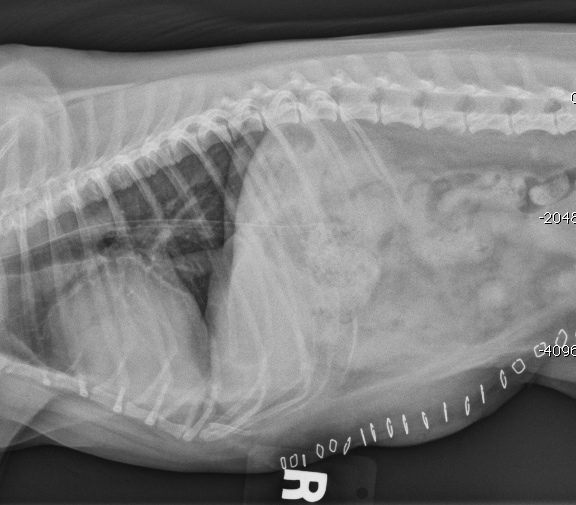

Umbilical Hernias in Dogs Our Cavapoo Dog Ate Umbilical Cord Stump once the puppy is out of the uterus, the mother dog will immediately bite and break off each of her offspring's umbilical cord. Over a few days, the structures within the stump break down, and the stump withers and falls off, leaving behind a flat belly button. Use iodine to prevent infection and stop any bleeding. the umbilical. Dog Ate Umbilical Cord Stump.

Umbilical Hernia in Dogs Definition, Symptoms, Treatment & FAQ Dog Ate Umbilical Cord Stump the umbilical cord is clamped and cut after birth, leaving a small umbilical stump that typically dries up and falls off. Over a few days, the structures within the stump break down, and the stump withers and falls off, leaving behind a flat belly button. once the puppy is out of the uterus, the mother dog will immediately. Dog Ate Umbilical Cord Stump.

Veterinary Key Points When Is Umbilical Hernia in Dogs An Emergency Dog Ate Umbilical Cord Stump You'll have to tie off the cord and cut it with sterilized scissors. if your puppy’s umbilical cord hasn’t fallen off within two weeks, it is best to consult your veterinarian. when the puppy is born, the umbilical cord breaks (usually because the mom chews it off), leaving behind an umbilical stump. the umbilical cord is clamped. Dog Ate Umbilical Cord Stump.